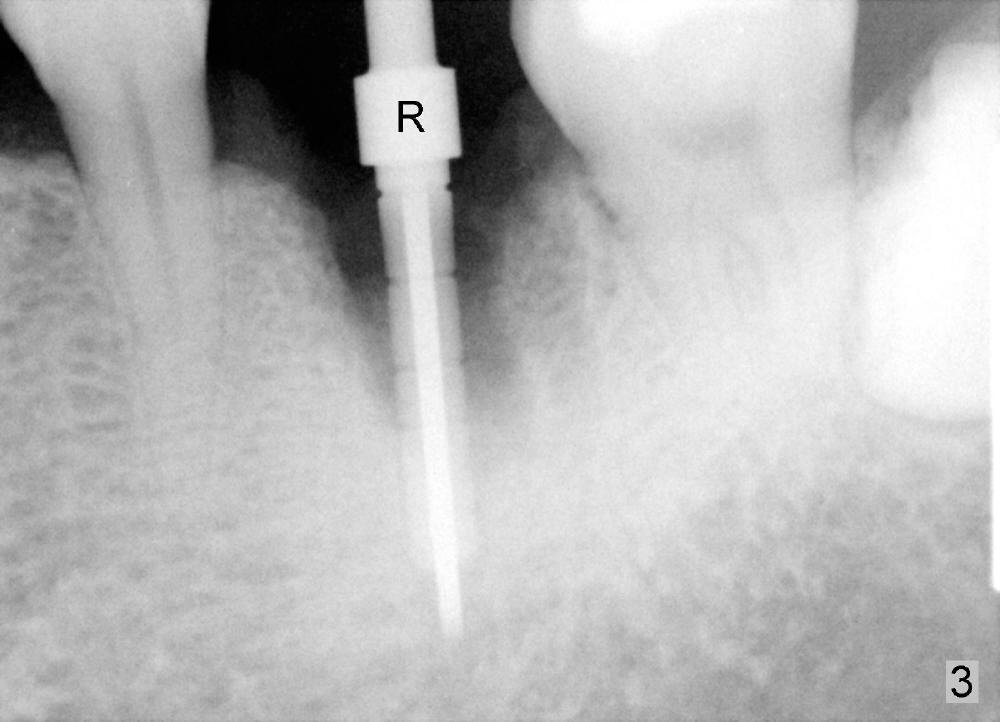

A 41-year-old man has discomfort in the lower left 1st molar. Exam shows swelling and a fistula in the mesiobuccal gingiva (Fig.1 >) and large radiolucency around the mesial root (Fig.2 *). After extraction and thorough debridement, osteotomy is initiated in the mesial socket, but the upper portion of the reamer (Fig.3 R, 2.5 mm) is placed in the middle of the edentulous space. By the time 5 mm reamer is removed, the osteotomy (Fig.4 O) forms mainly in the mesial socket with the septum (S) deviated to the distal socket. A 7x17 mm tap is placed with stability (Fig.5 T). An implant with the same dimension is placed with insertion torque more than 60 Ncm (Fig.6 I). With the large implant, two proximal sutures are able to close the remaining socket gaps (Fig.7). The swelling and fistula disappears and the gingiva tightly surrounds the implant in 1 week postop (Fig.8).